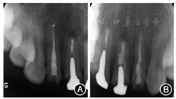

再治疗完成后即刻根尖X线片 A:

糊剂少量超填,

根尖3 mm倒充填致密;B:

恰填,

根尖3 mm倒充填致密

根尖3 mm倒充填致密见图8,图9,图10,图11。分别于术后3、6个月时复查根尖X线片,8个月时复查锥形束CT并分别进行临床检查。复查结果显示